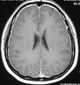

Ossification of falx cerebri